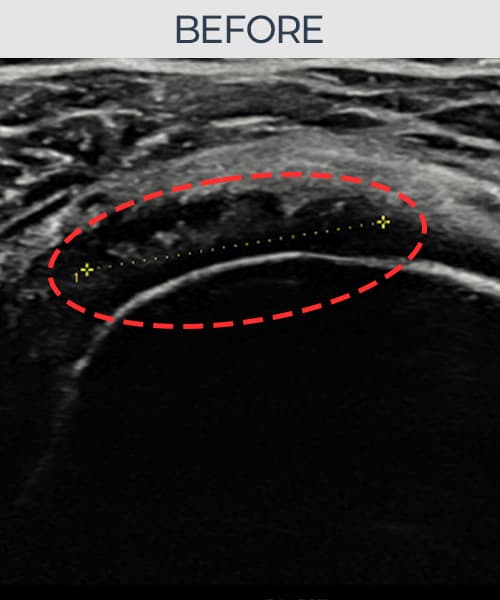

右侧 冈上肌腱 石灰化肌腱炎

14mm × 10mm